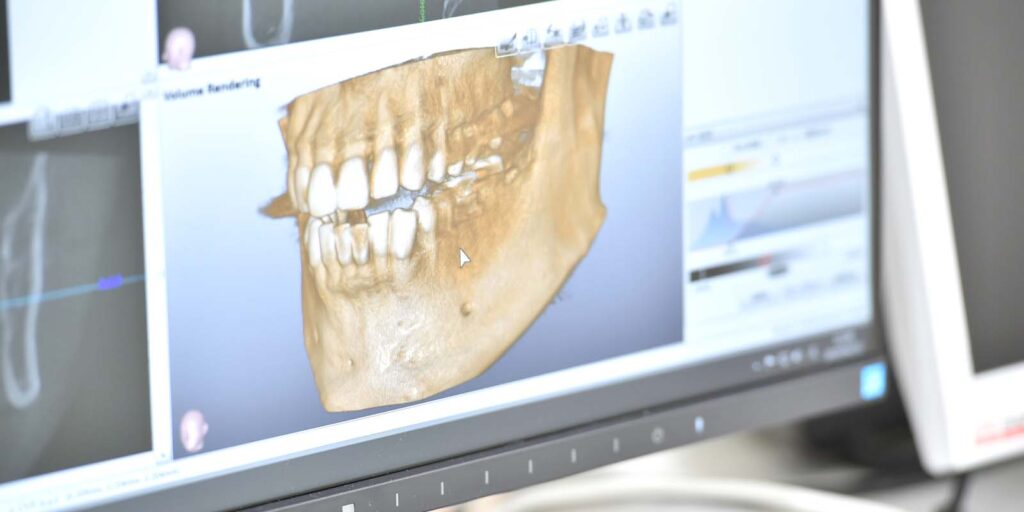

4.2 歯科用CT:骨と関節の微細な変形を3Dで捉える

従来の平面的なレントゲンでは見えなかった顎関節の内部構造や、歯の根っこの微細な破折を立体的に把握できます。「3Dで見て初めて原因がわかった」という症例も少なくありません。